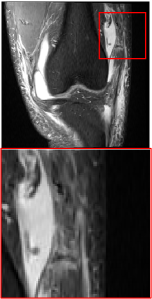

Figure 5 provides the qualitative comparison of the various methods on the four datasets at a scale of 4. The top, second, third, and bottom rows are the SR results under the FastMRI, clinical brain, clinical tumor and clinical pelvic datasets, respectively. The red boxes indicate the zoom-in region of complicated anatomical structures along with their corresponding error maps. Note that the brighter textures in the error maps, the lower the quality of the reconstructed images. As can be seen, compared to methods based on Transformers and CNNs, diffusion-based methods like DisC-Diff and DiffMSR (Ours) are capable of reconstructing high-realistic images with promising reconstruction metric scores (PSNR and SSIM). Nevertheless, while DisC-Diff can reconstruct high-precision MR images, it does not preserve the structure present in the original HR images, introducing some additional information that can affect medical diagnosis. In contrast, our method combines DM and PLWformer, which can preserve the original image’s structure while restoring high-frequency information.

In this section, we present more visual qualitative comparisons. Figures 8, 9, 10, and 11 show the reconstruction results of each method in FastMRI, clinical brain, clinical tumor, and clinical pelvic, respectively. As can be seen, although DisC-Diff can reconstruct MR images with high-frequency information, it fails to preserve the structure and content of the original Target HR image effectively, resulting in image distortion. In contrast, our proposed DiffMSR can restore high-frequency information while preserving the structure of the original HR image, indicating the effectiveness of the joint use of DM and PLWformer.